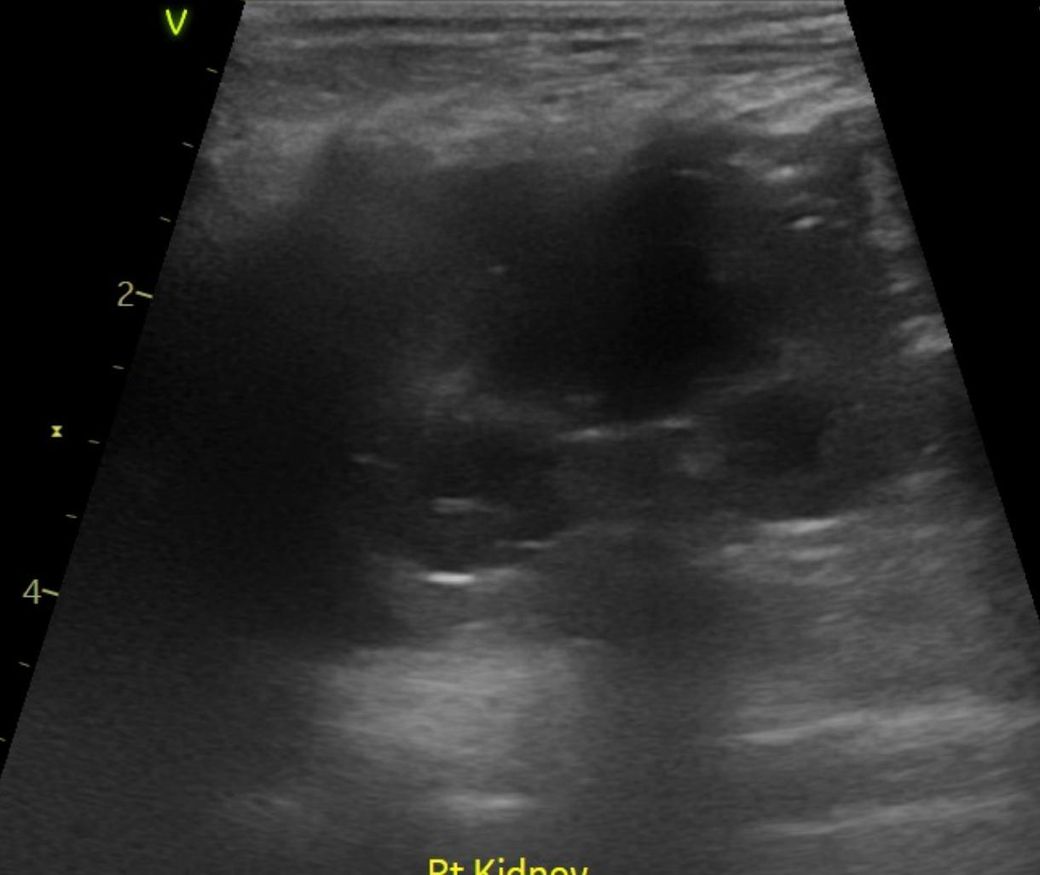

강아지 신장결석 칼슘옥살 스트루바이트 둘중 어느것 같아보이는지요?

강아지 신장결석 칼슘옥살 스트루바이트 둘중 어느것 같아보이는지요? 그냥 보시기에 만약에 판별이 가능하다면 알려주심 정말 감사하겠습니다. 병원만 3곳 다녔고 소변검사에 방광천자 제외하고 전부다 해봤는데 현재 6개월이 넘어갔는데 무슨 결석인지도 모르는 상태고 결석 크기는 신장 양쪽에 점점 커지고 있는 상황이라 이대로는 가만 있을수가 없어서 이렇게나마 질문글 올립니다.. 부디 알려주심 정말 한생명 살리는샘치고 정말 감사하겟습니다.

안녕하세요. 박창민 수의사입니다. 초음파 검사로 결석이 있는지, 위치나 크기, 개수, 형태 같은 정보는 확인할 수 있지만 결석의 정확한 종류나 성분까지는 알 수 없으며, 결석의 성분을 확인하려면 결석을 직접 채취해 분석하거나 소변 검사, X-ray, CT 등의 추가 검사가 필요합니다. 감사합니다.